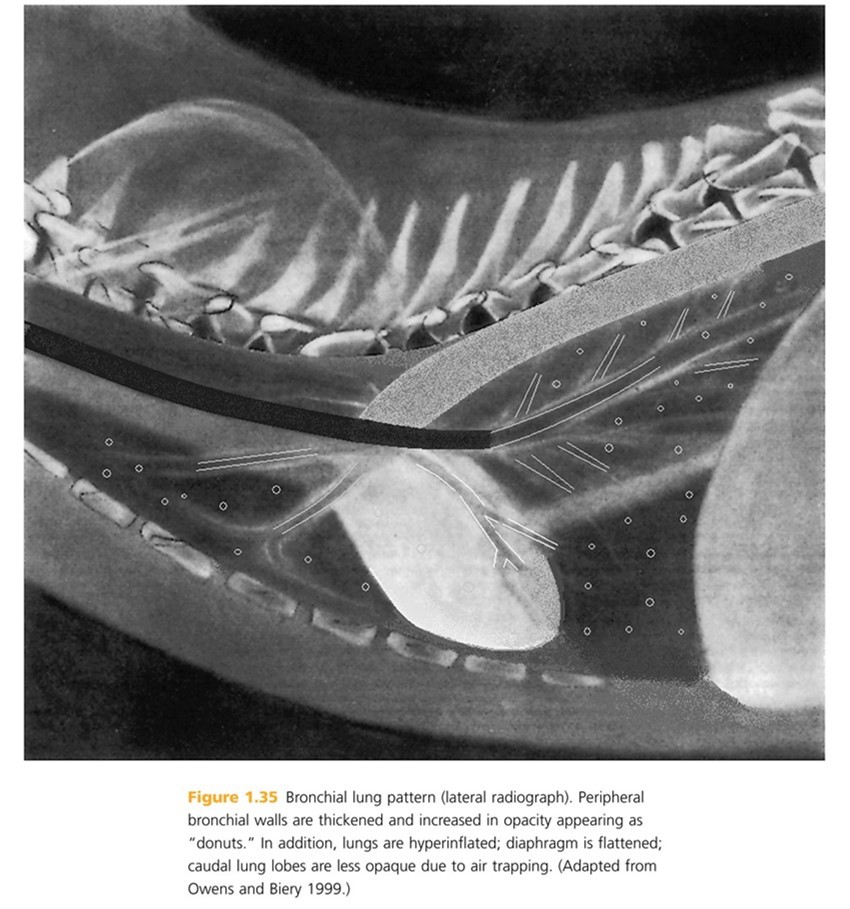

Thickened brochi viewed on-end appear as ____ ____.

Thick rings “donuts”

Thickened bronchi often do not ____ normally and appear as ____ ____ in profile. Paired blood vessels can be mistaken for thickened bronchial walls and therefore ______ are a more reliable finding with bronchial dz.

taper, parallel lines, “donuts”

Outer bronchial margins may become indistinct due to disease in adjacent lung parenchyma or peribronchial infiltrates which is called ____ ____. Vascular margins usually remain sharp and well defined if lung dz is confined to ____. Bronchi with enlarged diameters and irregular shapes (bronchiectasis) typically result from ____ _____.

Peribronchial cuffing, bronchi, chronic inflammation